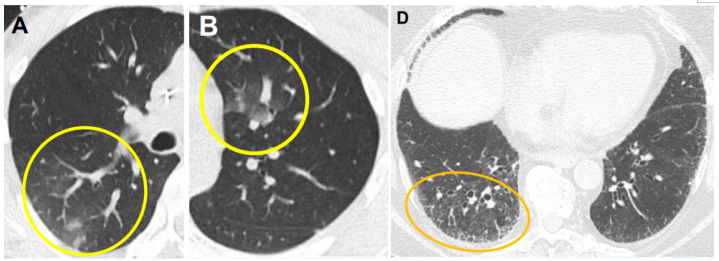

(1)感染性疾病:病毒性?细菌性?真菌?非典型病原体?吸入性肺炎?(2)非感染性疾病:心衰?急性肺栓塞?自身免疫性疾病?麻醉/手术相关肺损伤?急性间质性肺炎?回顾分析患者入院时胸部CT: 双肺靠近外周近胸膜处有轻微细小间质样改变(图4)。诊断:急性间质性肺炎;Ⅰ型呼吸衰竭;左肺下叶部分切除术后;高血压病。ECMO支持;呼吸机支持;甲泼尼松80 mg q12h,尼达尼布;镇静镇痛;抗感染;营养支持。ECMO第6天, 术后第18天, 肺部病变进一步加重(图5)。血气分析: pH 7.543, PaO2 154 mmHg, PaCO2 33.2 mmHg(ECMO, FiO2 100%, MV FiO2 60%)。术后第26天复查胸部CT未见改善。患者最终死亡。笔者团队也曾接诊过一例早期肺癌患者,2013年和2014年随访肺部结节均无明显变化。2015年胸部手术后2天,两肺变白(图6)。当时医生警惕性非常高,立刻行胸部CT检查并予相应治疗,患者最终存活。2022年RadioGraphics 杂志报道一例85岁女性腺癌患者奥希替尼治疗5个月后。图7-A和B为治疗前胸部CT图像,可见右肺中叶有肿块(A中箭头)。胸膜下区域磨玻璃改变和网状结构(箭头)提示存在间质性肺异常(Interstitial Lung Abnormalities,ILA)。治疗5个月后的轴位CT图像显示肿块(C中白色箭头)、弥漫性磨玻璃改变和合并症(黑色箭头)。图源:Radiographics, 2022, 42(7):1925-1939.另一例66岁右上肺鳞癌患者,术前CT显示肿块(图8-A中箭头)位于肺右上叶。轻度磨玻璃改变(箭头),提示ILA,见于胸膜下区域。图8-C和D为术后CT,显示弥漫性磨玻璃样改变和实变(箭头),牵引性支气管扩张症(图8-C中箭头),也可见胸腔积液(图8-D中箭头)。图源:Radiographics, 2022, 42(7):1925-1939.